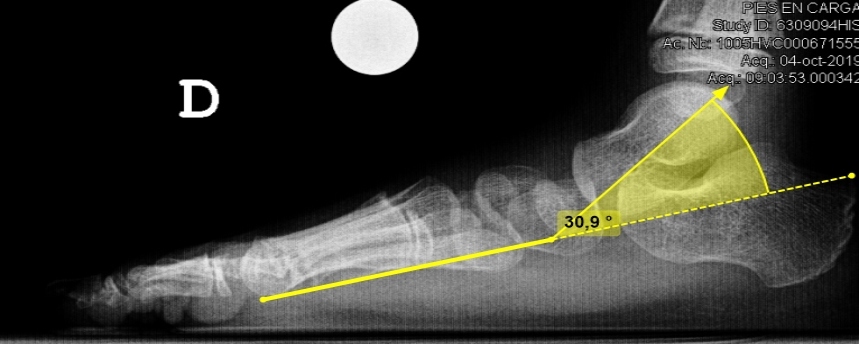

La primera técnica de imagen debe ser la radiografía convencional. Estas pueden objetivar un “os trigonum”, un proceso posterior del astrágalo hipertrófico, una fractura o una pseudoartrosis de la cola del astrágalo.